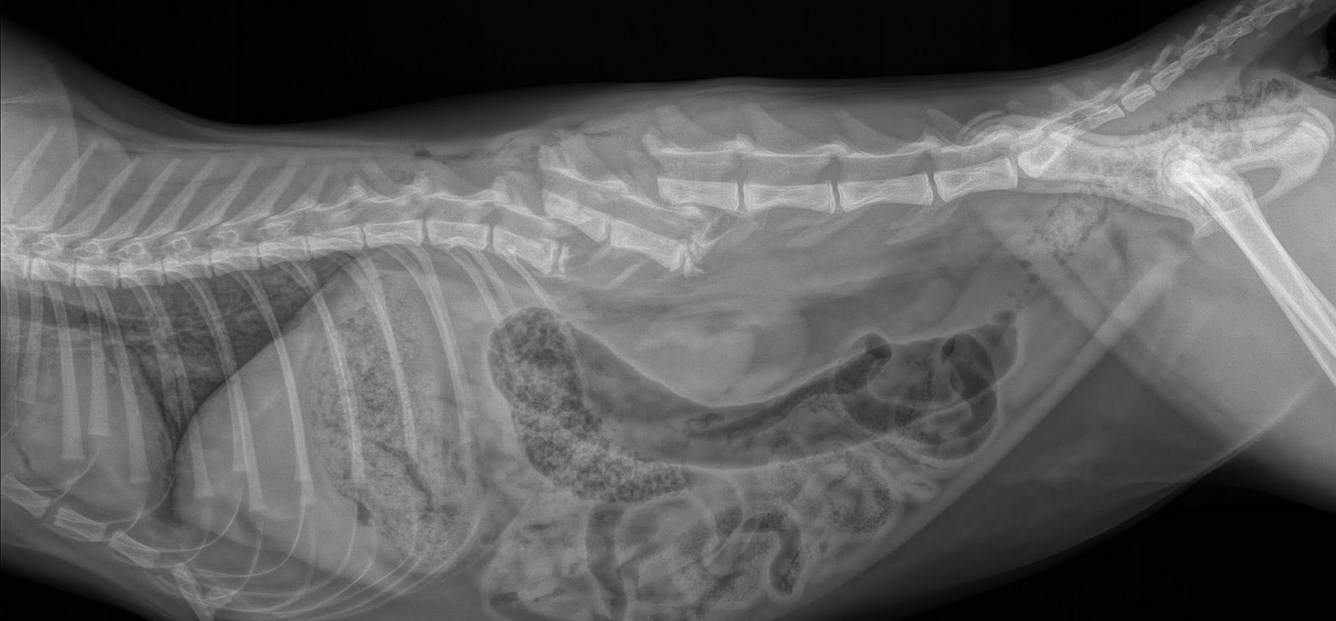

Травмы позвоночника у собак

Травмы

Причиной учащенного мочеиспускания могут быть травмы позвоночника, после получения которых были повреждены нервные окончания, а также спинномозговой канал. Если порода в силу своих физиологических особенностей имеет вытянутый позвоночник, то вероятность развития проблемы увеличивается еще больше.

Это хроническая патология, которая сопровождается обильным выделением прозрачной мочи с низким удельным весом. Развивается на фоне нарушения реабсорбции воды в организме животного, а именно на участках канальцев почек. Развивается преимущественно после травм позвоночника и черепа, кровоизлияний и опухолевых процессов.